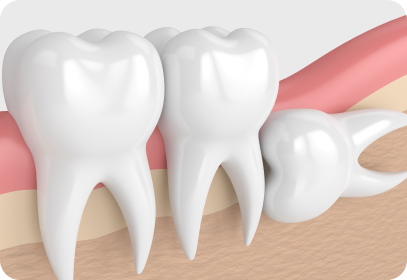

불완전 돌출 사랑니

비정상적인 위치에 매복되어 자란 사랑니는

염증과 통증을 일으킬 수 있으므로

발치하는 것이 좋습니다.